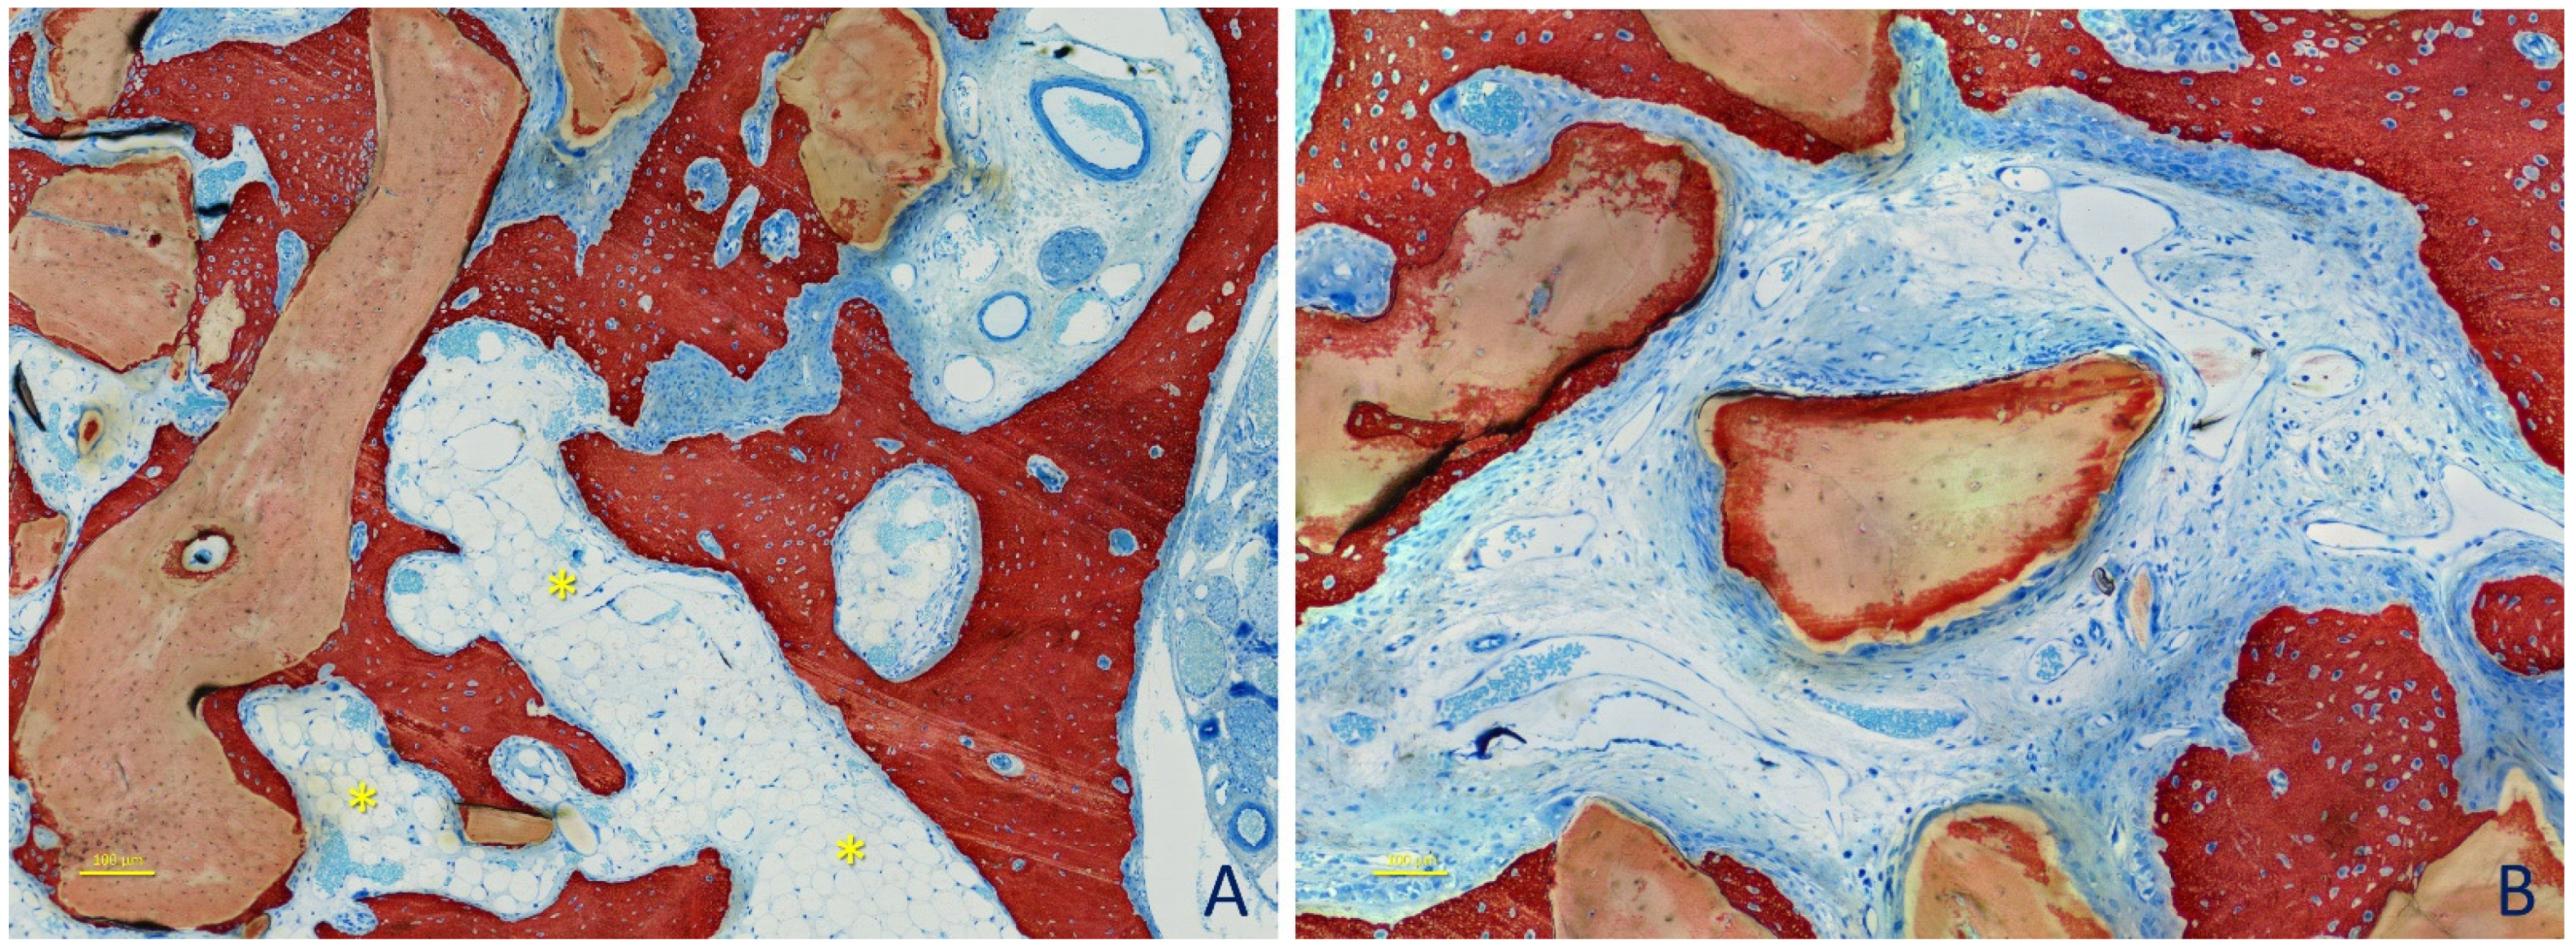

3. Results